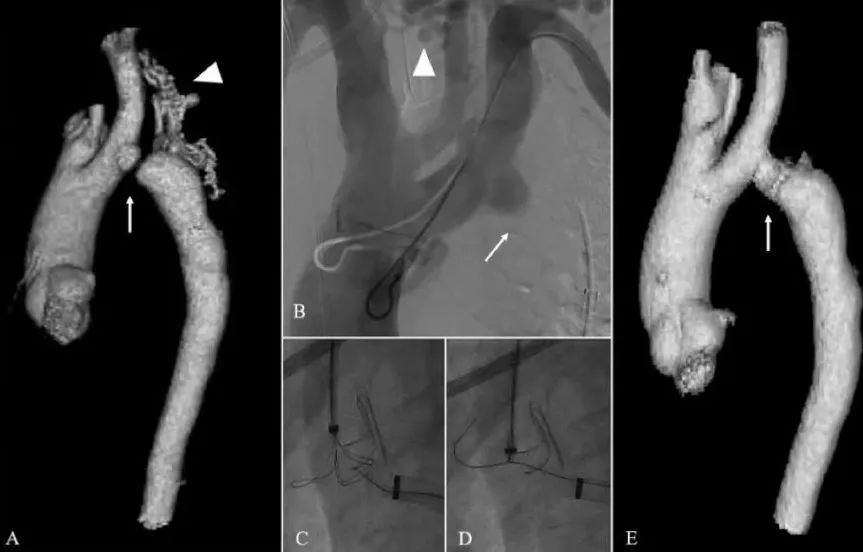

图3

(A)主动脉闭锁患者的CTA3D重建(A-E)和血管造影,可见主动脉闭锁(白色箭头),有一个延伸的侧支供应远端主动脉(白色三角)(B)DSA显示主动脉闭塞(白色箭头)和侧支网络(白色三角)(C)(D)带电导丝穿过主动脉闭塞处并被捕获(E)覆膜支架重建闭塞处后的主动脉CTA3D重建。